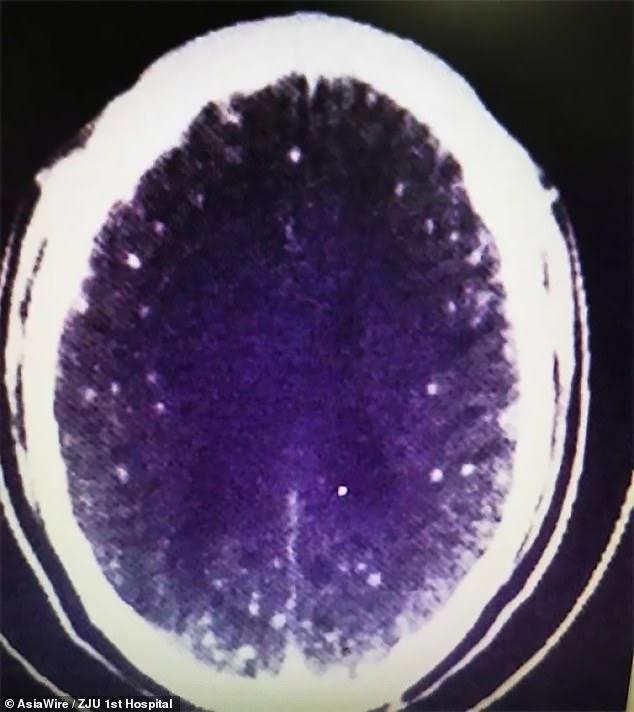

Dr Huang Jianrong, from the Affiliated Hospital of Zhejiang University School of Medicine, ordered brain and chest MRI scans. These revealed that Mr Zhu's brain and chest were riddled with cysts of the pork tapeworm. Dr Huang said: 'He not only had numerous space-occupying lesions in his brain, but he also had cysts in his lungs and chest muscles.' Different patients respond differently to the infection depending on where the parasites occupy.

'In this case, he had seizures and lost consciousness, but others with cysts in their lungs might cough a lot.' Dr Huang added: 'We killed the larvae using antiparasitic drugs and prescribed medication to protect his organs and reduce any side effects brought on by the treatment.' Phase one of the treatment has now concluded after a successful week. Now we'll run further tests.' It is still unclear whether Mr Zhu will suffer any long-term effects from the tapeworm infection.